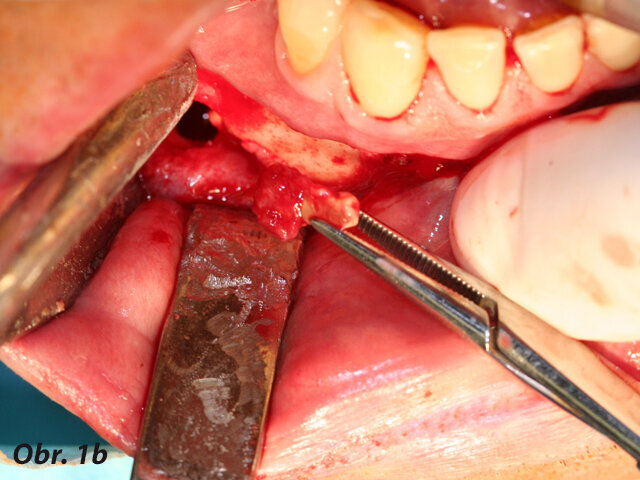

Při výkonech dentoalveolární chirurgie používáme koncovky osteoplastické, jejichž pomocí lze šetrně odpreparovat kostní tkáň nad retinovanými zuby ať v případě jejich následující extrakce nebo v případě následné fenestrace či tunelizace, kdy je možné jejich následné ortodontické zařazení do zubního oblouku.

Opatrnost doporučujeme při preparaci v blízkosti skloviny – pokud totiž dojde k přímému kontaktu piezochirurgické koncovky se sklovinou zubu, nelze vyloučit rozvoj mikrofraktur skloviny, která má odlišné mechanické vlastnosti než kost.

Osteotomické koncovky používáme pouze k separaci zubních tkání, které budeme závěrem extrahovat. S výhodou pro situace, kdy plánujeme okamžitou implantaci, je provedení extrakce pomocí piezochirurgie, ne však způsobem, který je často demonstrován na různých školeních a workshopech. Tam bývá stomatologům často doporučováno použití extrakční koncovky místo periotomu. To může vést k přehřátí okolní kosti a následným komplikacím ve smyslu alveolitis sicca. Extrakce v těchto situacích by měla být provedena jako postupná separace kořene a jeho odstranění po částech, přičemž okolní kostní tkáně se snažíme dotýkat minimálně, abychom nepoškodili kostní buňky zubního lůžka.